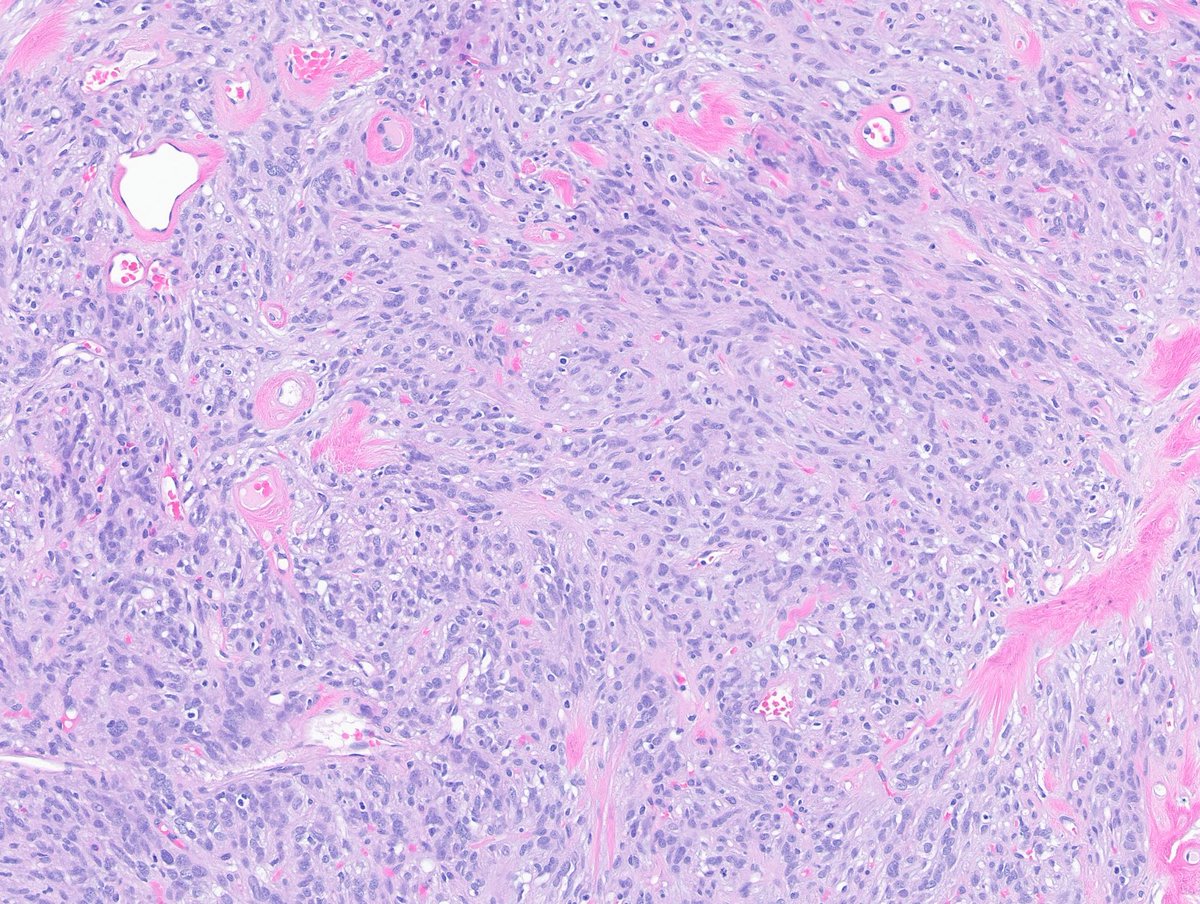

Adult male. Retroperitoneal mass. #PathX #PathTwitter #BSTPath

SumantaDas_7's tweet image. Adult male. Retroperitoneal mass.

#PathX #PathTwitter #BSTPath